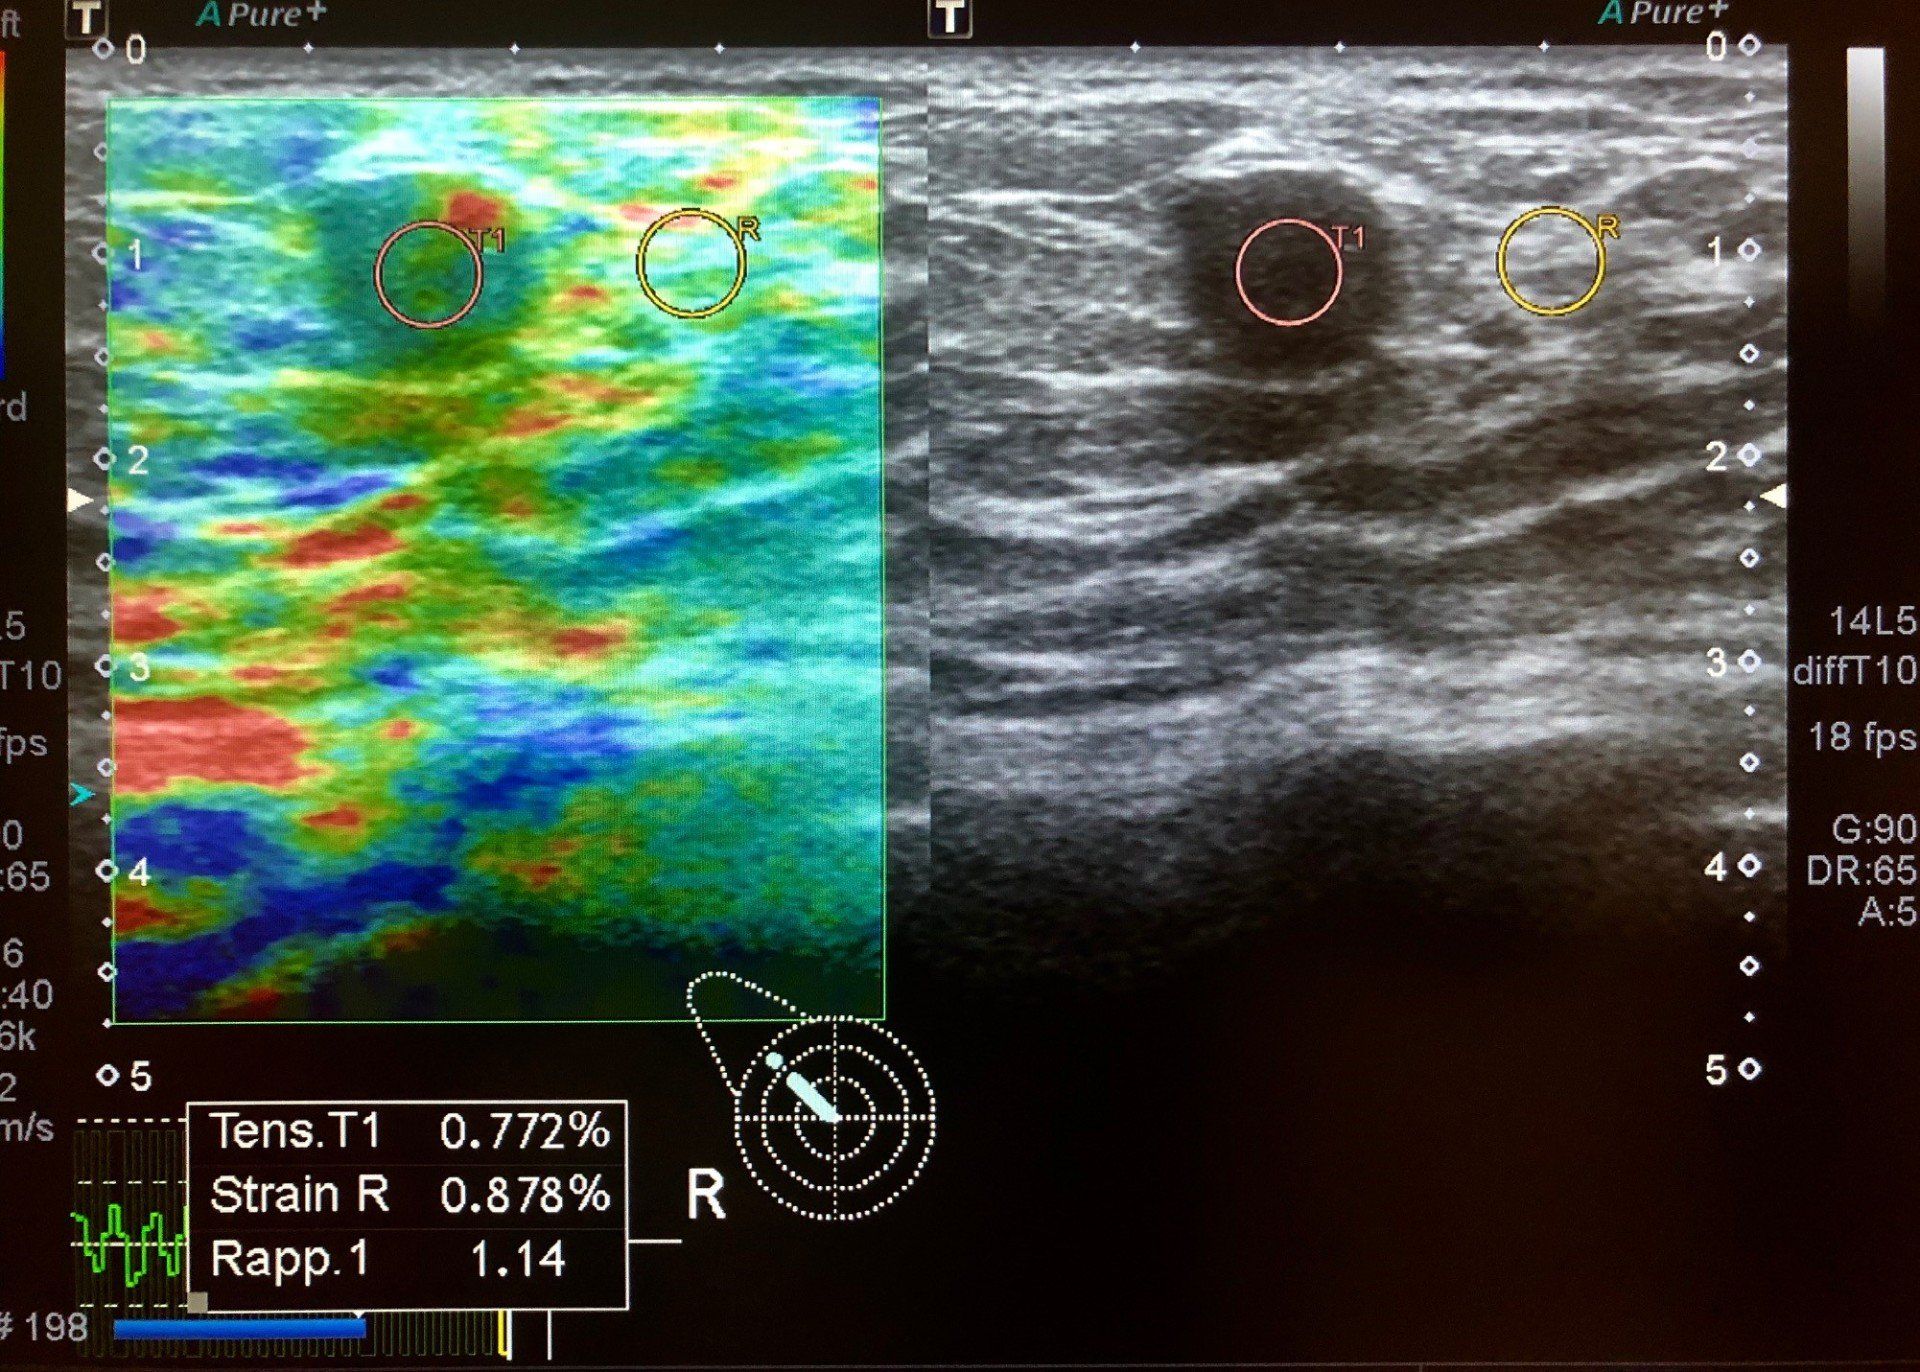

Elastosonografia

L'elastosonografia è una metodica ecografica che fornisce informazioni riguardo l'elasticità dei tessuti. Viene usata prevalentemente nella patologia tiroidea, mammaria, muscolo tendinea e testicolare. L'elasticità di un tessuto viene espressa con una scala cromatica (per convenzione rosso: elasticità elevata - verde: elasticità media - blu: assenza di elasticità) che caratterizza una lesione nodulare secondo la sua elasticità.